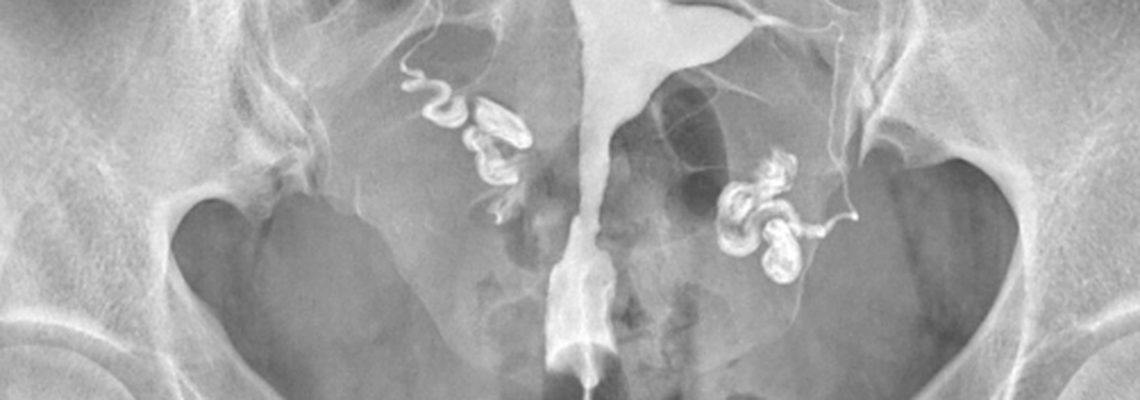

Cet examen consiste à prendre des radiographies du pelvis après injection par le col d’un produit radio‑opaque qui passe ensuite dans l’utérus et les trompes.

Il injecte ensuite doucement un produit radio‑opaque par le col qui va permettre d’opacifier l’utérus, puis les trompes si elles sont perméables. Différents clichés radiographiques sont alors réalisés.